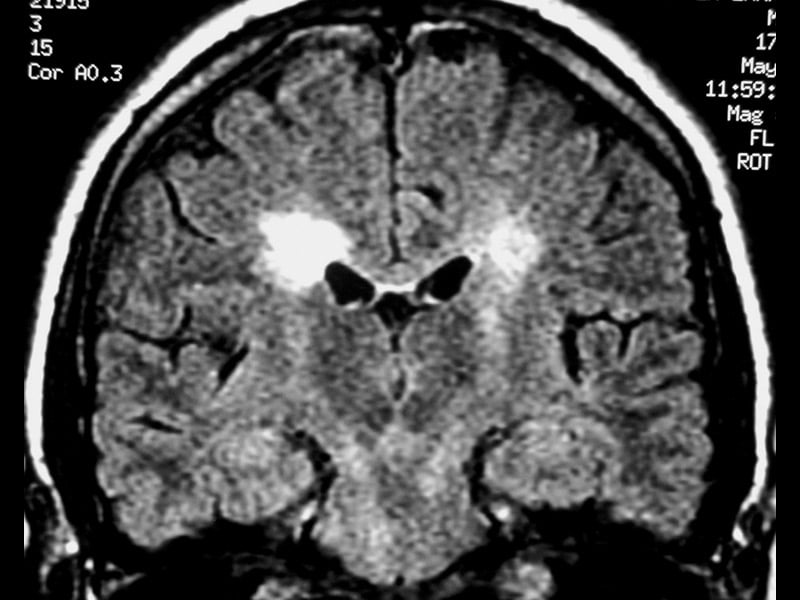

Информация о диссеминированном рассеянном энцефаломиелите